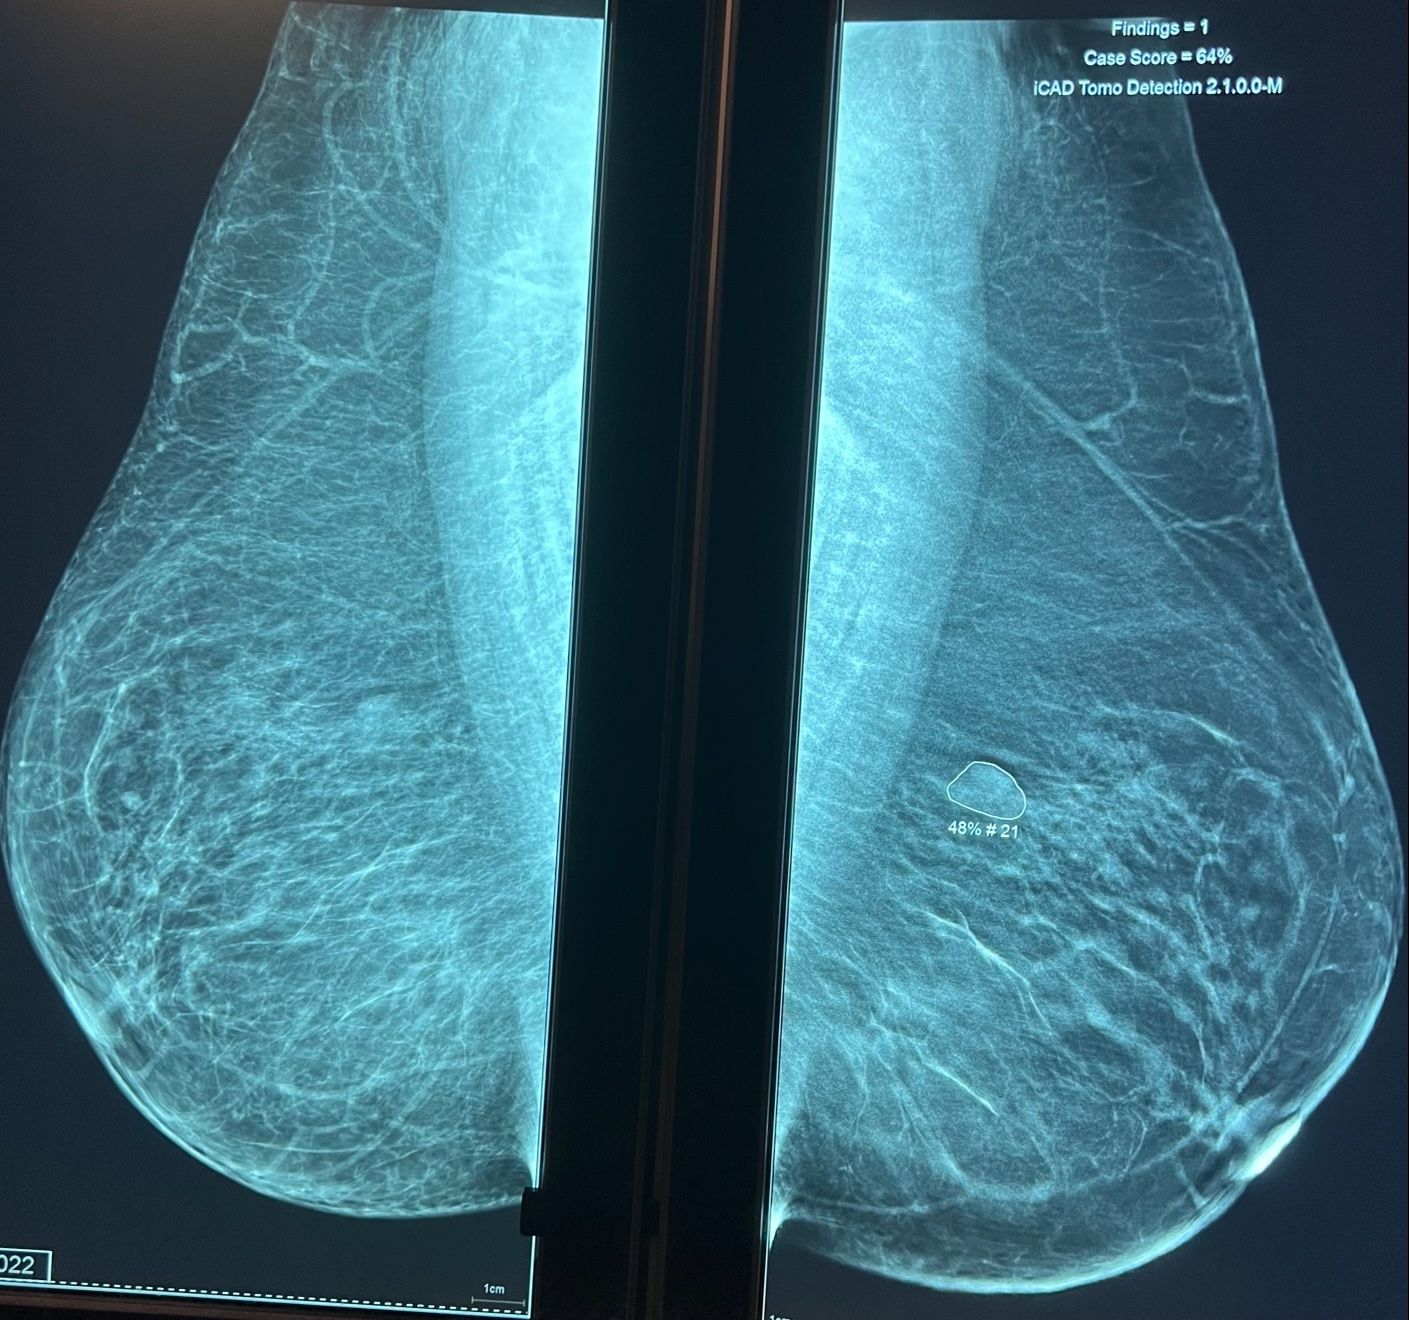

Le radiologue lit votre mammographie et dans un second temps utilise sur le mammographie numérique un CAD (computed aided detection), de dernière génération (ICAD pour imagerie 2D et tomosynthèse 3D) qui va marquer les micro-calcifications (marquées par un carré) et les masses (marquées par un rond) avec la valeur prédictive positve en faveur d'une lésion maligne.

Micro-calcifications (carré) Petite masse, distorsion architecturale (rond)

aleur prédictive de lésion maligne 48%